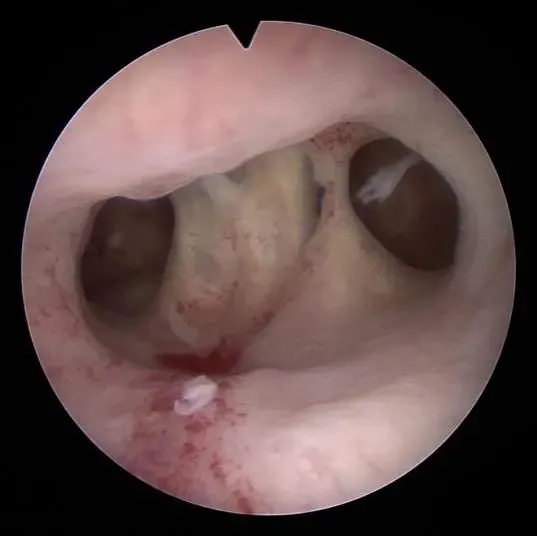

杨东琴主任介绍,王女士之前做过的人流手术很可能就是宫腔粘连的诱因。根据王女士的情况,杨主任为她进行了宫腔镜下宫腔粘连分离术。为避免粘连分离后再次粘连,在术后为她进行了子宫内膜修复情况及宫腔形态评估,并根据其情况为其进行后续调理及治疗。术后2个月,王女士就顺利怀孕。

宫腹腔镜术前

杨主任介绍,宫腔镜可直接检视宫腔内病变,比传统的诊刮、子宫造影乃至B超更直观、更准确、更可靠。能减少误诊、漏诊的可能,提高诊断的准确性。有效治疗宫腔粘连、疏通输卵管近端堵塞,打通生育“关卡”。